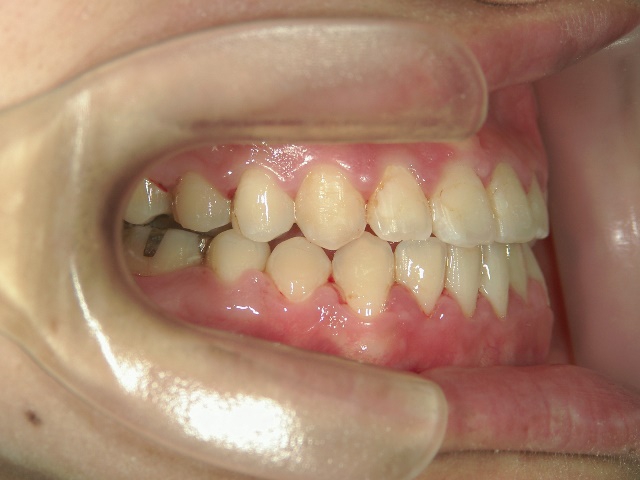

矯正歯科 治療前矯正歯科 治療前

主訴:受け口(反対咬合)を治したい

矯正歯科 治療前 急速拡大装置で上顎を広げた後、ワイヤーへ移行 非抜歯

no.31_7964_治療前_右 .JPGno.31_7964_治療前_正面 .JPGno.31_7964_治療前_左 .JPG